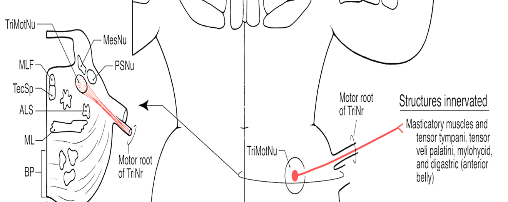

Figure 4 illustrates the extensive neural control the Trigeminal Nerve (CN V) has over chewing, swallowing, and breathing simultaneously, as CN V is used by 3 other cranial nerves (CN III, VII, IX) to reach their end structures. The posterior teeth (part of CNV, Div III) directly communicate with the center of the brain (RetF), and 4 cranial nerves to ensure food does not enter the lungs.

Figure 4 – The Trigeminal nerve aids the OculomotorTrochlear, Facial, and Glossopharyngeal nerves in reaching their end structures. Posterior tooth pulp and PDL motor fibers influence many structures that 4 cranial nerves and the RetF control. Adapted from https://quizlet.com/132746657/chapter-15-the-autonomic-nervous-system-ganglia-flash-cards/.